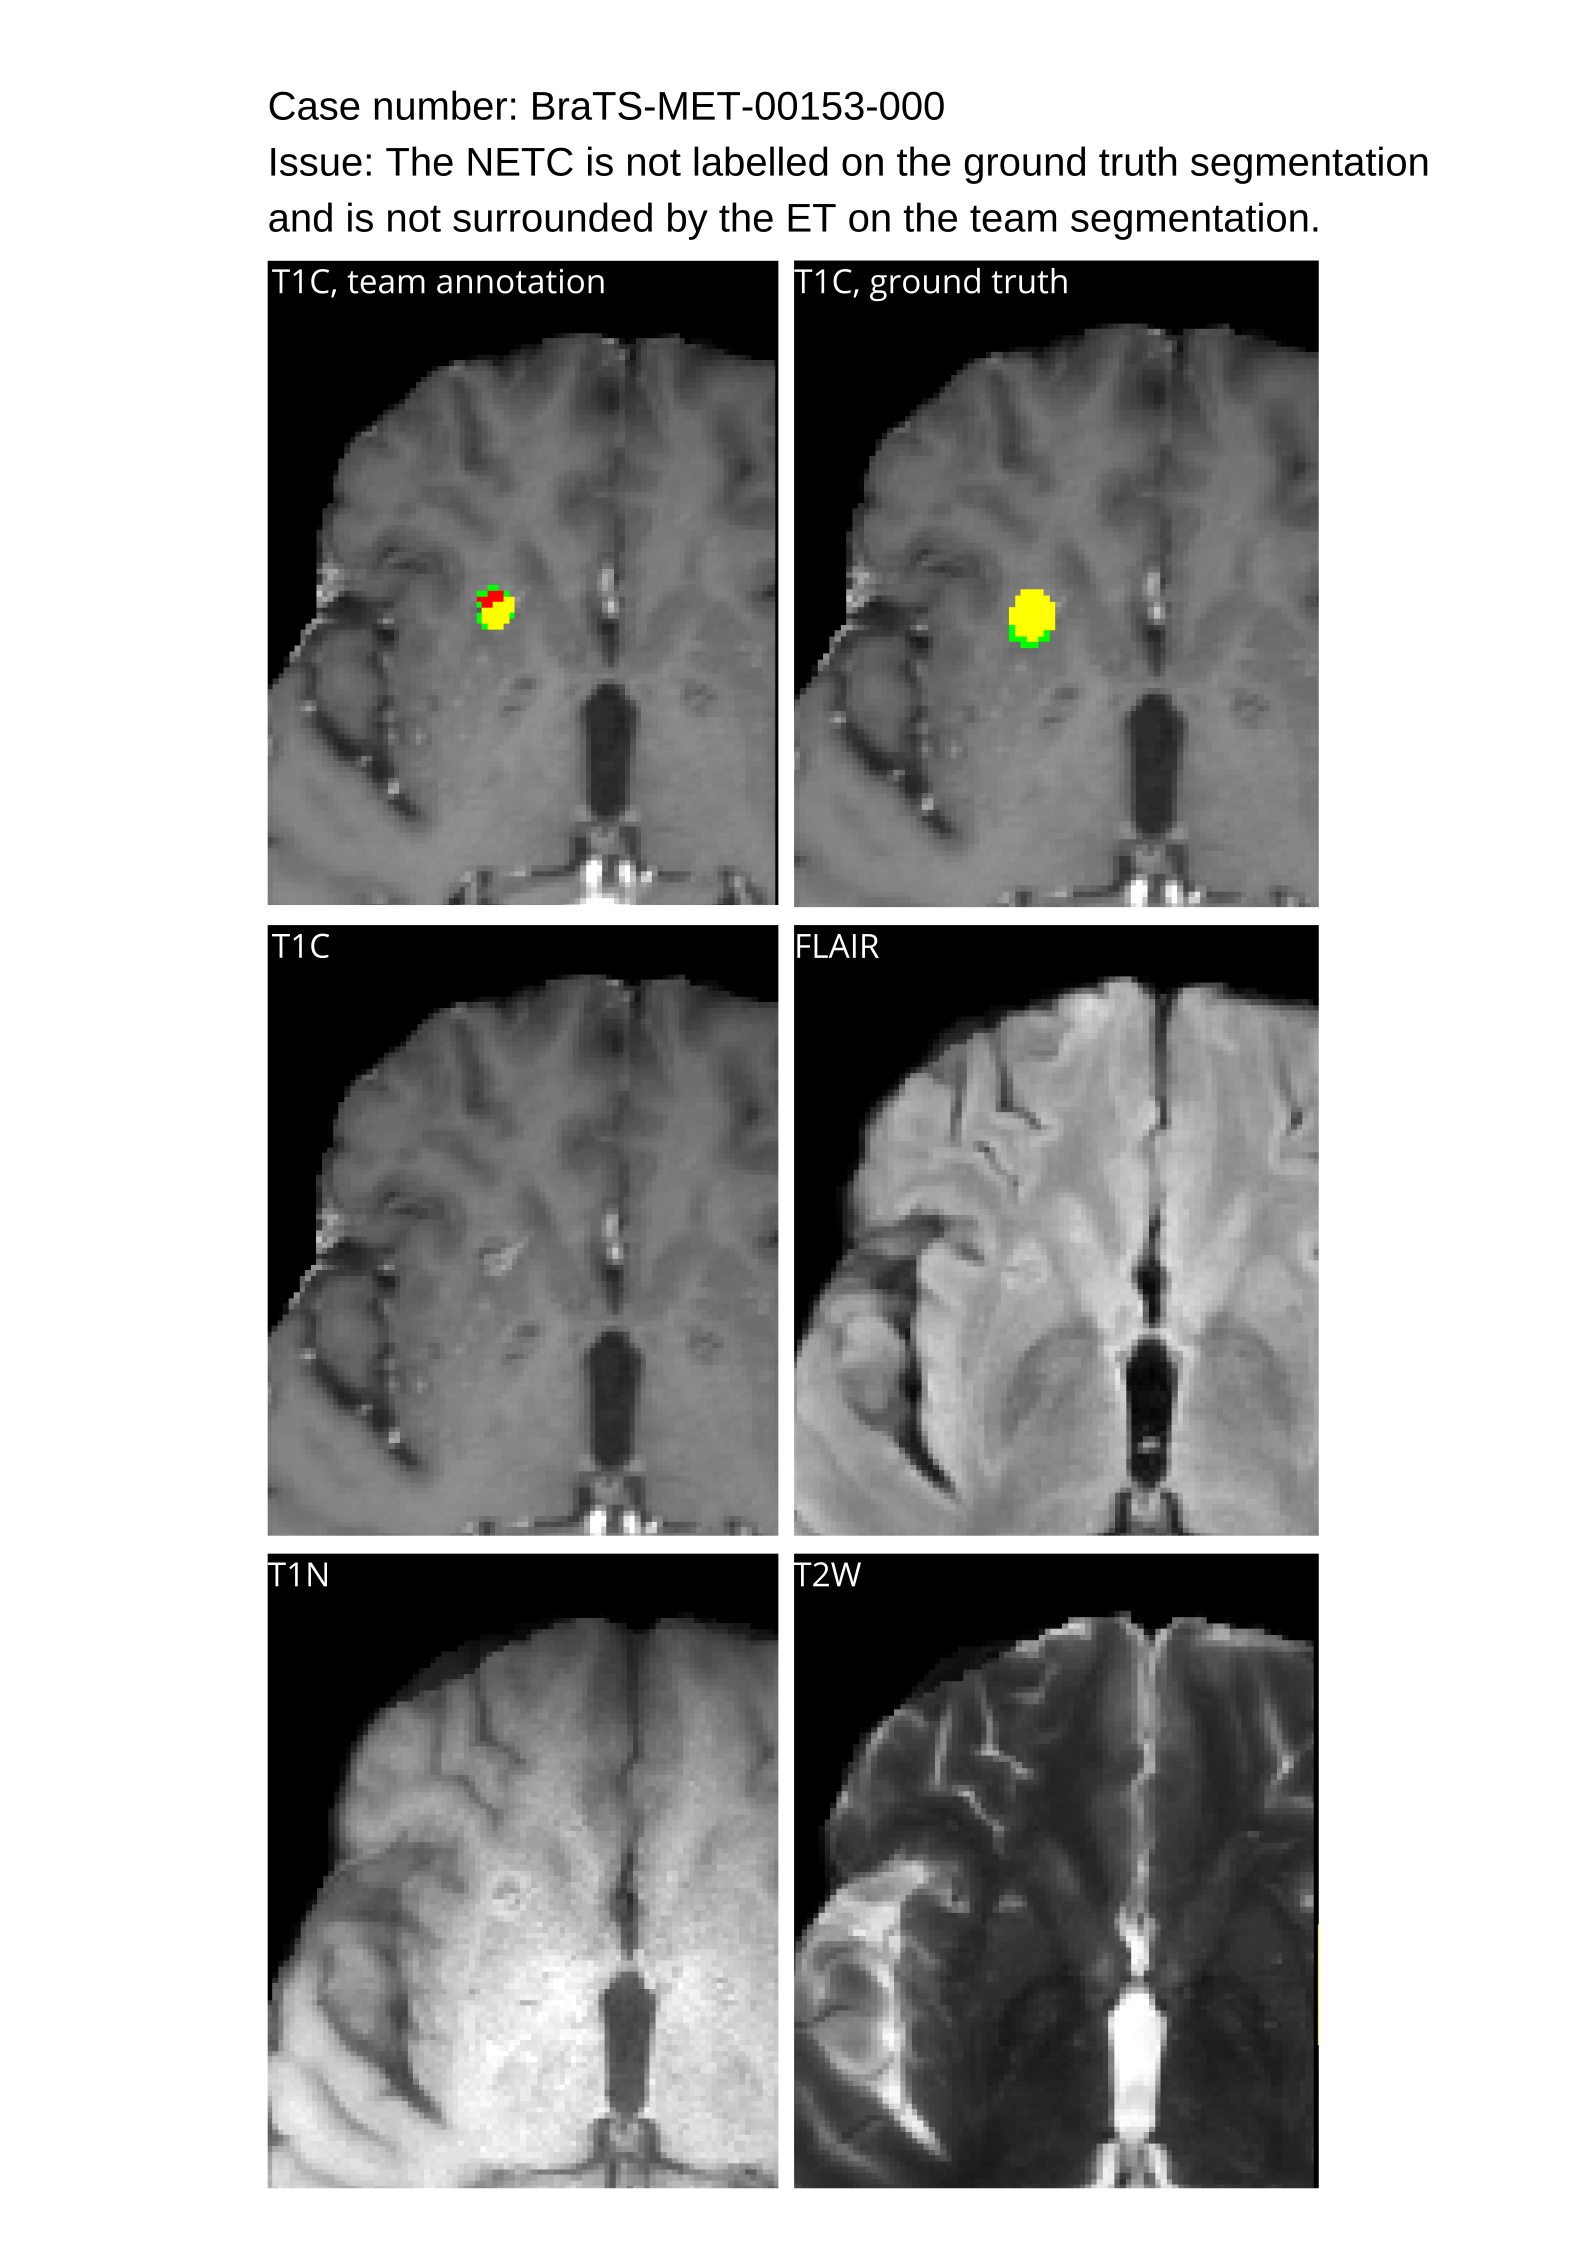

4.3 Tumor Labels

The annotation of tumor sub-regions aligned with Visually AcceSAble Rembrandt Images (VASARI) feature visibility and encompassed three labels: Gd-enhancing tumor (ET - label 3), surrounding non-enhancing FLAIR hyperintensity (SNFH - label 2), and the non-enhancing tumor core (NETC – label 1). ET is described as the enhancing portion of the tumor, characterized by areas of hyperintensity in T1Gd that are brighter than T1. NETC is identified as the presumed necrotic core of the tumor, which is evident as a non-enhancing focus surrounded by enhancing tumor. SNFH is defined as the peritumoral edema and tumor infiltrated tissue, indicated by the abnormal hyperintense signal on the T2-FLAIR images, which includes the infiltrative non-enhancing tumor, as well as vasogenic edema in the peritumoral region. In previous BraTS challenges, ET was segmented as label 4. However, starting from BraTS 2023, ET has been segmented as label 3 for consistency. The sub-regions are shown in Figure 2.

4.9 Common Errors of Automated Segmentations

Based on observations from previous BraTS challenges, common errors in automated segmentations were identified. The most typical errors in the current challenge included:

2. 2.

Segmentation of white matter changes from microvascular disease. Peritumoral edema segmentations were checked by neuroradiology attendings and modified.